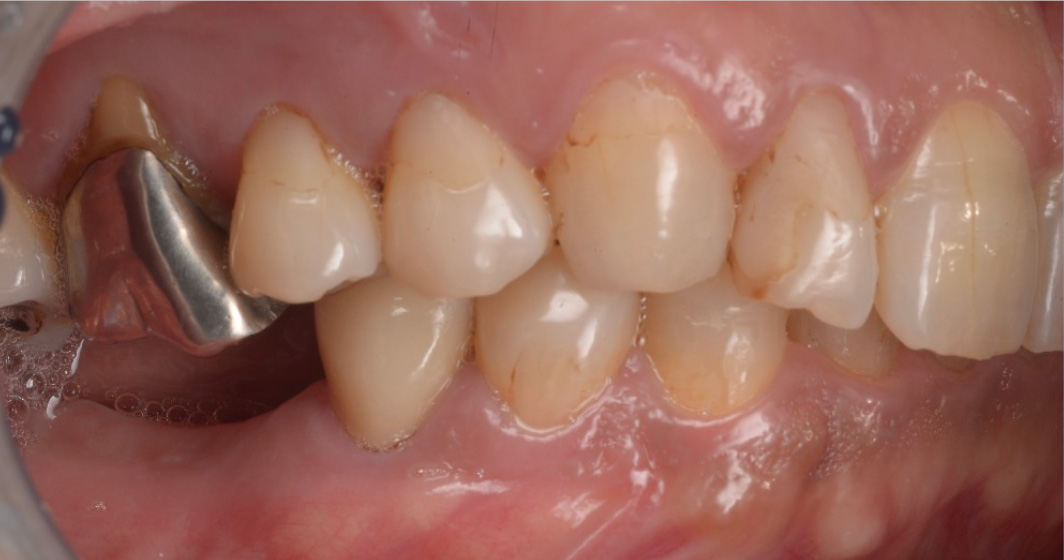

上唇の腫脹を認め、CT検査にて根尖部に嚢胞様透過像を認めた。左上の前歯が不自然に大きく噛み合わせが強くなっていたことがフレアアップの一因と考える。精密根管治療を行い、感染経路を遮断したのち歯根端切除術にて嚢胞を摘出した。

治療中